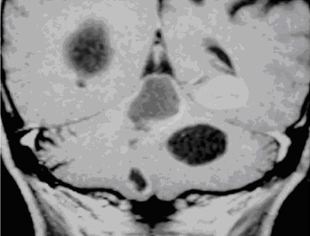

4. Mô phỏng lập kế hoạch xạ phẫu

Có thể sử dụng hình ảnh CT để mô phỏng lập kế hoạch xạ phẫu cho dao gamma quay, nhưng tốt nhất là sử dụng hình ảnh MRI sọ não được chụp trên máy cộng hưởng từ mô phỏng 1,5 Tesla có gắn hệ thống định vị laser 3 chiều với khoảng cách giữa các lát cắt 2mm.

Hình 8. Hình ảnh lập kế hoạch xạ phẫu u não di căn trên phim MRI